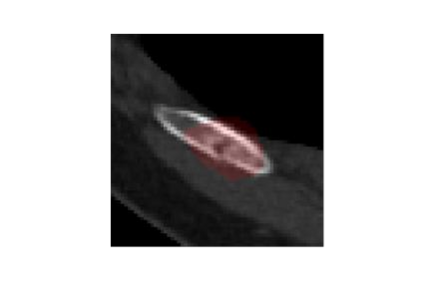

Rib fractures are a common and potentially severe injury that can be challenging and labor-intensive to detect in CT scans. While there have been efforts to address this field, the lack of large-scale annotated datasets and evaluation benchmarks has hindered the development and validation of deep learning algorithms. To address this issue, the RibFrac Challenge was introduced, providing a benchmark dataset of over 5,000 rib fractures from 660 CT scans, with voxel-level instance mask annotations and diagnosis labels for four clinical categories (buckle, nondisplaced, displaced, or segmental). The challenge includes two tracks: a detection (instance segmentation) track evaluated by an FROC-style metric and a classification track evaluated by an F1-style metric. During the MICCAI 2020 challenge period, 243 results were evaluated, and seven teams were invited to participate in the challenge summary. The analysis revealed that several top rib fracture detection solutions achieved performance comparable or even better than human experts. Nevertheless, the current rib fracture classification solutions are hardly clinically applicable, which can be an interesting area in the future. As an active benchmark and research resource, the data and online evaluation of the RibFrac Challenge are available at the challenge website. As an independent contribution, we have also extended our previous internal baseline by incorporating recent advancements in large-scale pretrained networks and point-based rib segmentation techniques. The resulting FracNet+ demonstrates competitive performance in rib fracture detection, which lays a foundation for further research and development in AI-assisted rib fracture detection and diagnosis.